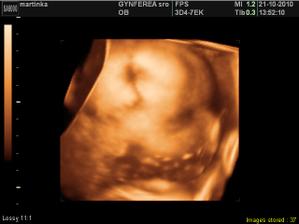

tijuska krasna fotecka

Neuveriteľný zázrak 🙂 Gratulujem a prajem, aby ste to dotiahli do úspešného konca 🙂

Utvrdzuješ ma v tom, že zázraky skutočne existujú Zo ♥ ti prajem, aby tvoje tehulkovanie bolo neskutočne krásnym zážitkom!!!!!! ... s ešte viac neuveriteľným zázrakom menom DIEŤA!